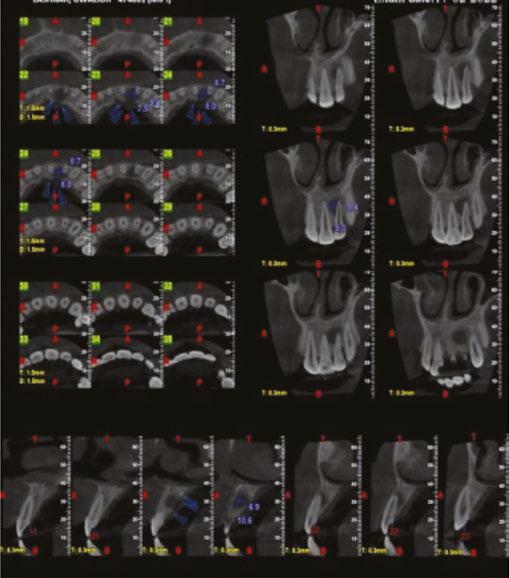

Figures 2-4: 2. Working-length radiograph CBCT of the involved tooth. 3. Master cone radiograph. 4. Postoperative radiograph Figures 5 and 6: 1- year follow-up CBCT image

Figure 7: Preoperative radiograph Figure 9: 1-year follow-up CBCT Figure 10: 1-year follow-up CBCT Figure 8: CBCT of involved tooth

Radiographs of a 61-year-old female who presented with pulp necrosis and asymptomatic apical periodontitis. Dr. Wiseman performed minimal instrumentation in this case due to the dilacerated and calcified canals. The mesial canal has a 45 degree curvature in the apical 1/3 of the root. The GentleWave procedure was completed. Radiographs viewed are the preoperative 2D and 3D images and the postoperative image

Radiographs of an 80-year-old male who presented with pulp necrosis and asymptomatic apical periodontitis. Dr. Wiseman performed minimal instrumentation in this case due to the dilacerated and calcified canals. The mesial canal has a 45 degree curvature in the apical 1/3 of the root. The GentleWave procedure was completed. Radiographs viewed are the preoperative 2D and 3D images and the postoperative image

Radiographs of a 15-year-old male who presented with previous treatment and asymptomatic apical periodontitis. When Dr. Wiseman removed all the gutta percha, the mesial canals were blocked. The GentleWave procedure was completed. The final radiograph reveals sealer that was able to flow into the apical 1/3 of the mesial roots. Radiographs viewed are the preoperative 2D and 3D images and the postoperative image